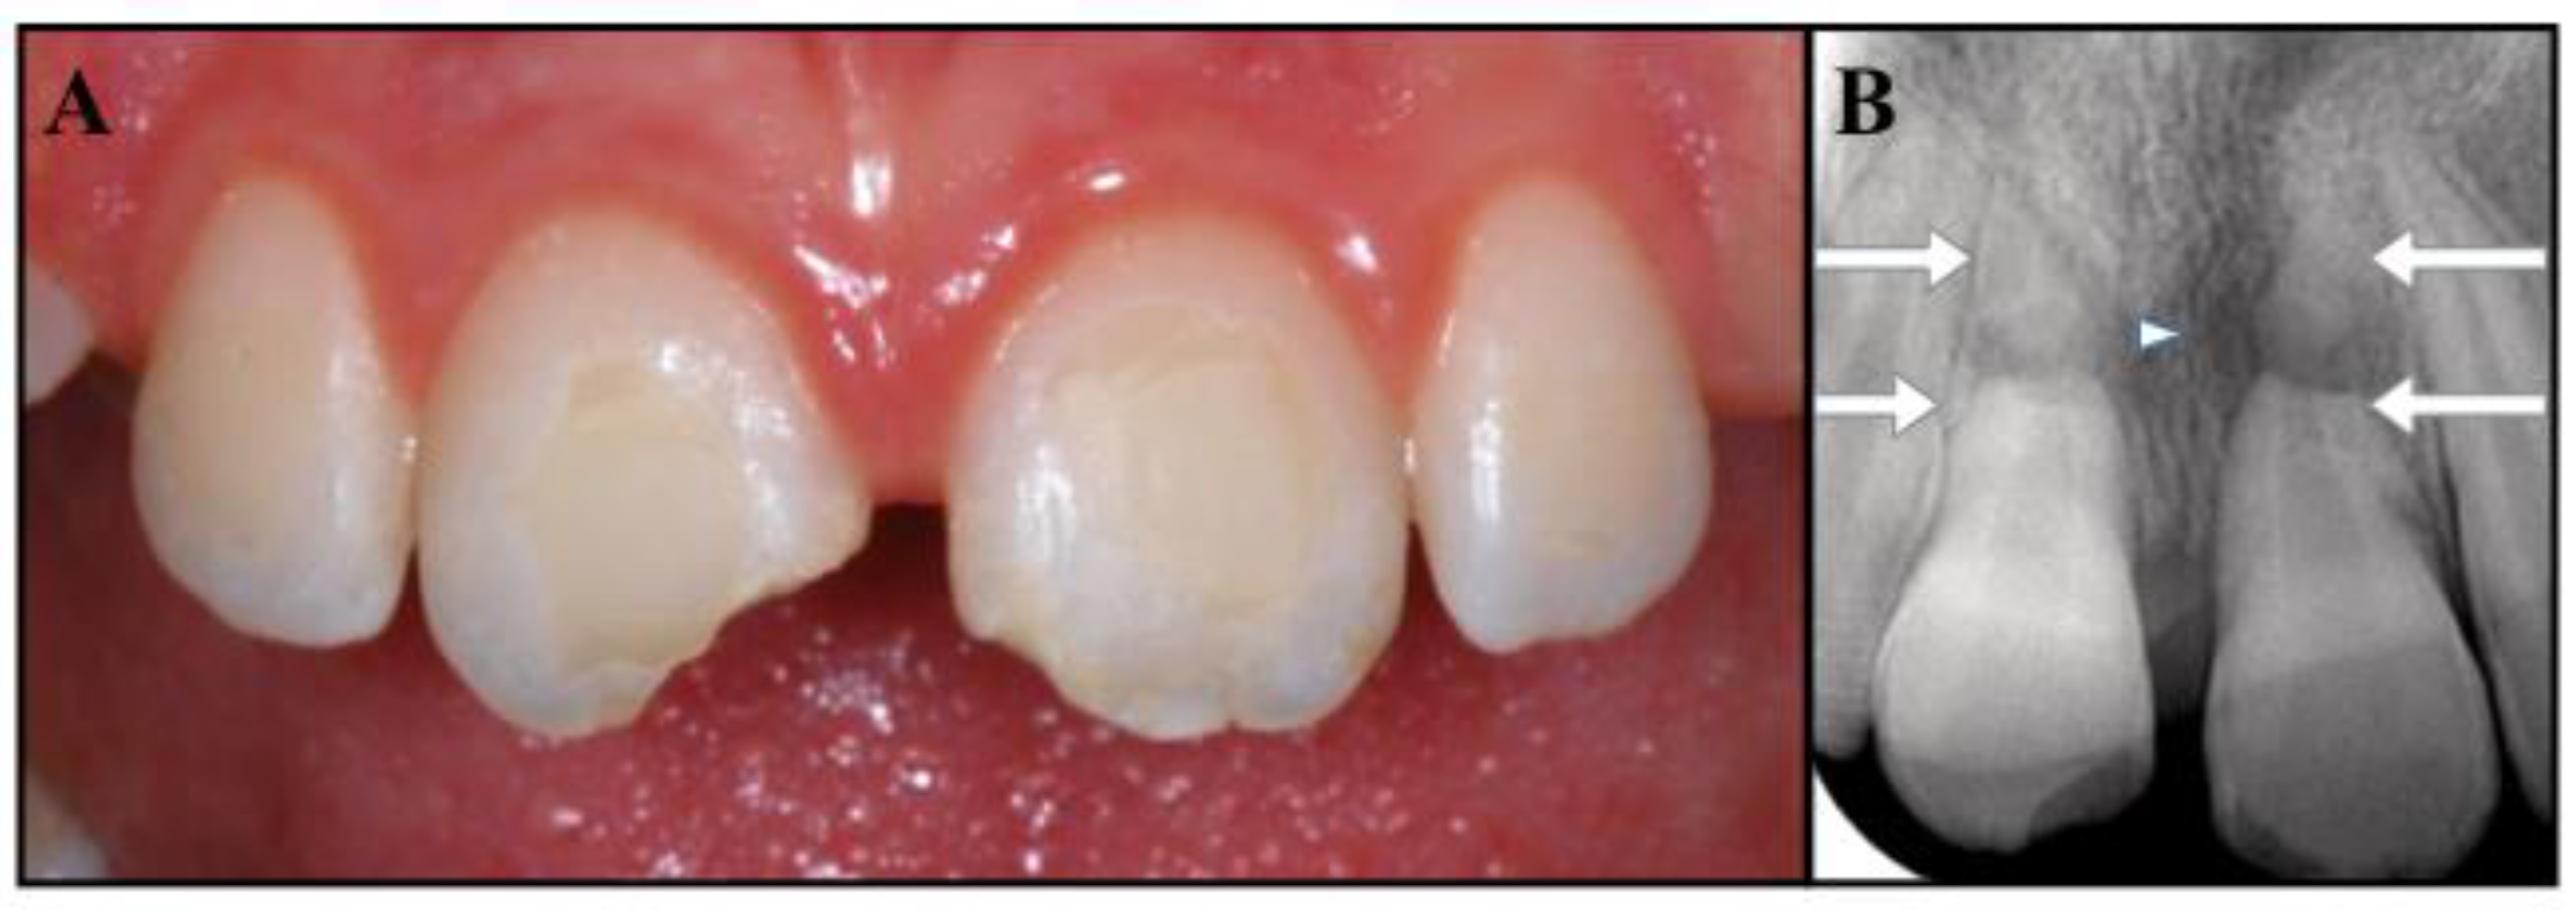

Figure 3.

(A) Root canal filling with of tooth #2.1. (B) Post obturation and restoration of tooth #2.1. (C) The 6-month follow-up periapical radiograph reveals the radiolucency of tooth #1.1 (arrow). (D) Root canal filling with Portland cement and resin restoration of tooth #1.1. (E) Image from the 12-month follow-up. (F) Image from the 30-month follow-up.

Six months later, tooth #1.1 no longer responded to the sensitivity tests and the periapical radiograph showed a radiolucent area at the fracture site of the root (Figure 3C).

Tooth #1.1 was diagnosed with pulp necrosis and apical periodontitis in the coronal fragment, and an apexification procedure was performed with the same protocol as the one previously described for tooth #2.1 (Figure 3D). We then filled the canal with Portland cement (Aureoseal, Ogna lab, Muggiò, Italy).

The follow-up was carried out according to schedule. At 30 months, the patient was free of symptoms, and the periapical radiographs showed healthy periodontal tissues around both the fractured roots and the apical fragments, while the fractured areas seemed to have healed, with hard tissue deposition (Figure 4C,D). The tooth eruption was assessed to be normal with the continued development of the alveolar ridge. Undesirably, tooth # 2.1 showed mild signs of discoloration. The patient was informed that the clinical and radiographic follow-up would continue once a year for at least another three years, and ideally for as long as possible. She was also made aware that further considerations will be necessary upon completion of the permanent dentition.